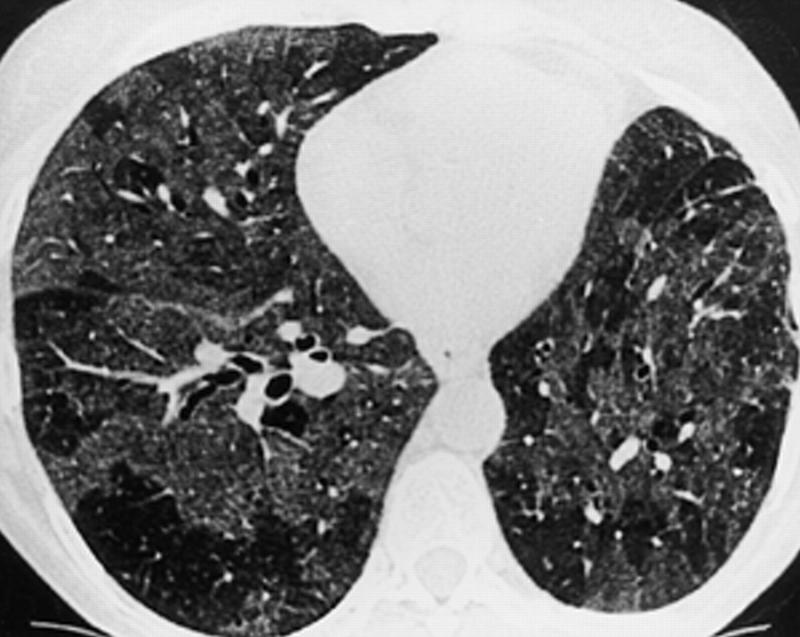

КТВР органов грудной клетки — это основной метод визуализации для выявления и оценки лимфоидной интерстициальной пневмонии. Она позволяет детально рассмотреть структуру легких и обнаружить характерные изменения. Для лимфоидной интерстициальной пневмонии характерны следующие радиологические признаки:

- Зоны «матового стекла»: Участки пониженной плотности легочной ткани, которые могут быть обусловлены клеточной инфильтрацией и легким фиброзом.

- Перибронховаскулярное утолщение: Утолщение стенок бронхов и сосудов, окруженных лимфоцитарными инфильтратами.

- Мелкие перибронхиальные узелки: Могут встречаться в области бронхов и бронхиол.

- Кистозные изменения: Множественные тонкостенные кисты различного размера, часто ассоциированные с сосудисто-бронхиальными структурами, являются одним из наиболее характерных, хотя и неспецифичных признаков ЛИП.

- Утолщение междольковых перегородок: Свидетельствует о вовлечении интерстиция.

- Генерализованная лимфаденопатия: Увеличение внутригрудных лимфатических узлов может наблюдаться, но обычно не является доминирующим признаком.

Характерная картина на КТВР может навести на мысль о лимфоидной интерстициальной пневмонии, но для окончательного диагноза часто требуется гистологическое подтверждение.